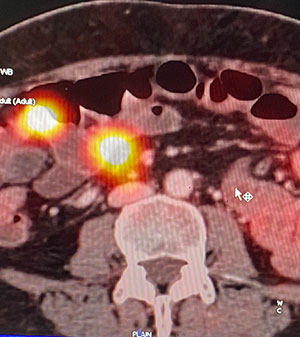

53 year old lady presented with weight loss, weakness, anorexia, loose motions, abdominal discomfort & melena. Her CT scan of the abdomen & pelvis showed a small intestinal tumor with lymph node mass suggestive of a NET. Further work up with DOTA-PET confirmed it as a NET. It also showed a tiny metastatic tumor in the liver. Tumor marker work up with chromogranin and 24 hour urinary 5-HIAA showed the former having normal levels and the later raised significantly further confirming the SI-NET with a functioning component like a carcinoid disease.